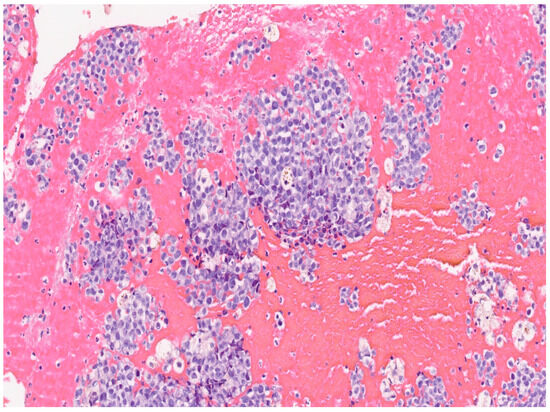

Primary Malignant Melanoma of The Endocervix Uteri and Outpatient Hysteroscopy as a Diagnostic Tool: Case Report and Literature Overview

3. Results